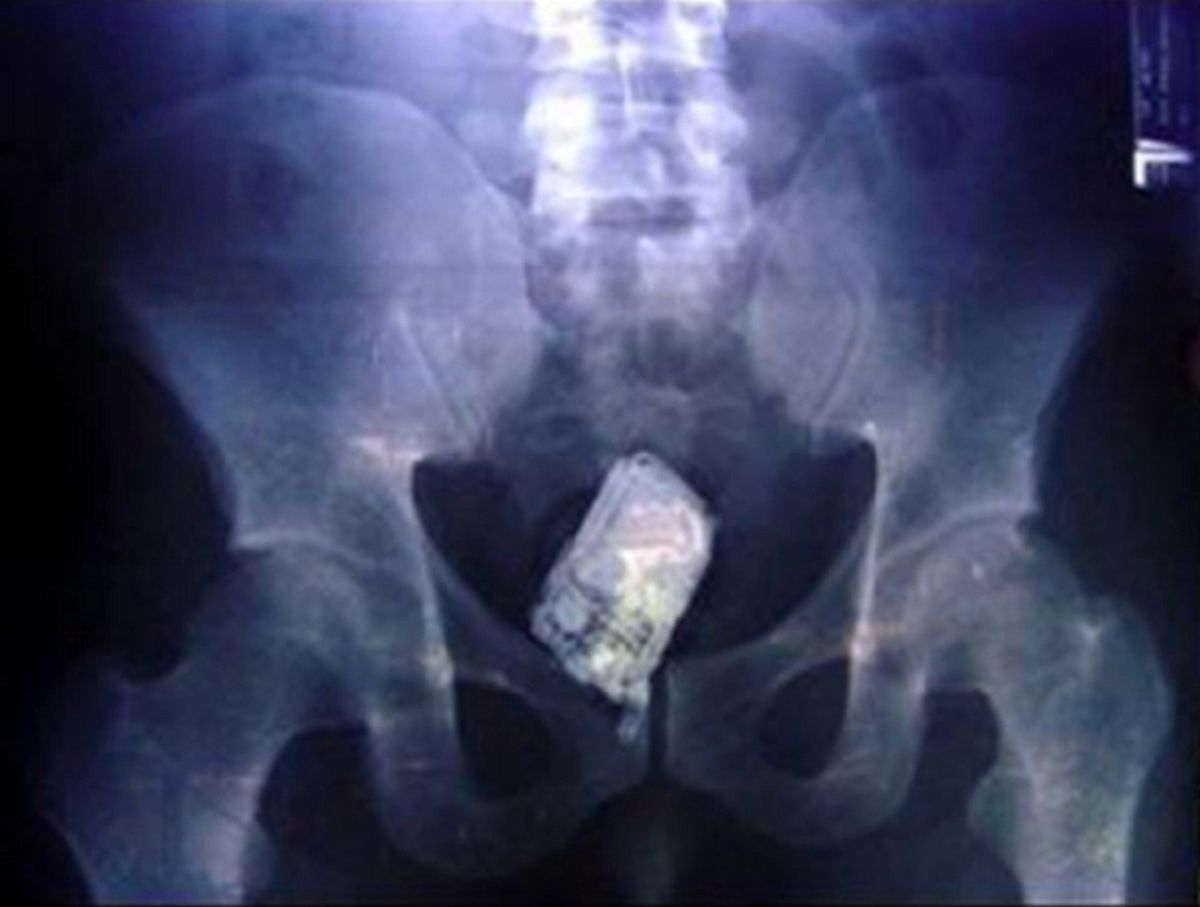

/ 8Telefon komórkowy

Ponoć ktoś zapomniał się przy zabawie wibracjami...